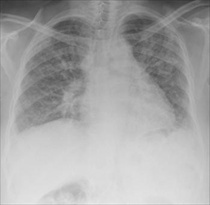

and patient healthcare standards can be improved.Cystic fibrosis (CF) is a life-threatening recessive genetic disease which causes severe malfunctioning of the exocrine glands, respiratory system and gastrointestinal tract. Diagnosis frequently takes place only once symptoms are already obvious, thereby delaying disease management and risking irreversible damage to the vital organs. The median age of survival is around 30 years, with death most commonly due to cardio-respiratory complications.